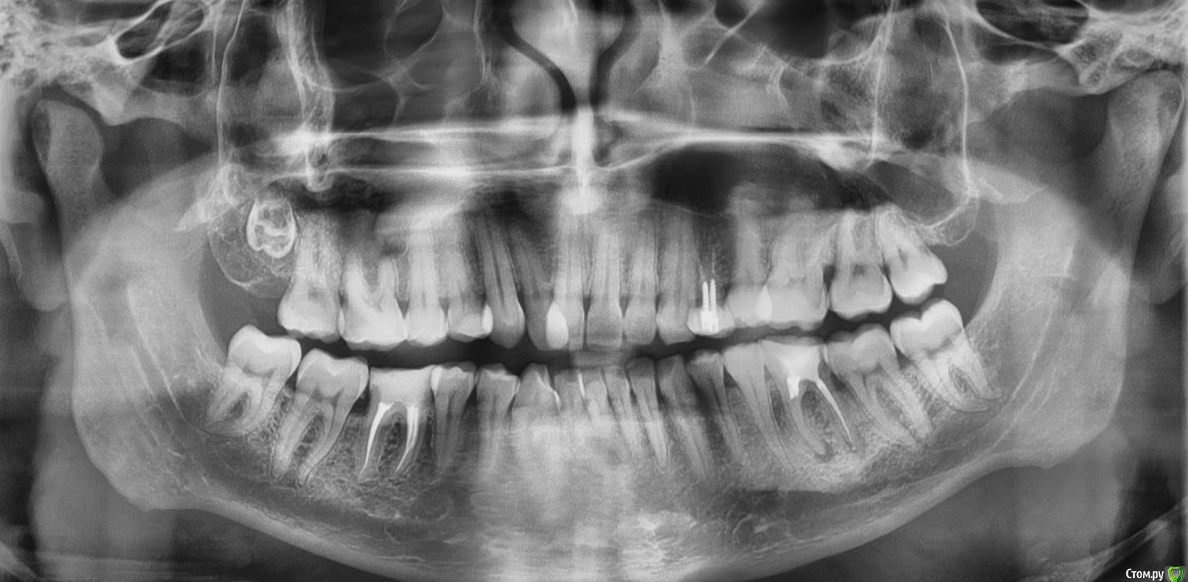

SkyWay Опубликовано 13 июля, 2020 Поделиться Опубликовано 13 июля, 2020 Добрый день.Задумался в 30 лет ставить брекеты, хотя в интернете есть разные мнения, особенно часто говорят, что не стоит в таком возрасте выпрямлять прикус, из-за того что зубы потом разъедутся, но и не мало, что никогда не поздно. В общем сам вопрос, все зубы на месте, но из 4 зубов мудрости, один так и не вырос.Вот как он выглядит: Будут ли что делать с этим зубом в случае установки брекет системы? или нет смысла его трогать? Ссылка на комментарий

SkyWay Опубликовано 17 июля, 2020 Автор Поделиться Опубликовано 17 июля, 2020 На консультации ортодонт сказал удалить все 8ки, в том числе и этот ретированый.Хирург по снимку сказал, что он вроде даже не вырос, и чтобы его удалить его надо высверливать, и разнести полчелюсти..Вот теперь ещё менее понятно что делать Ссылка на комментарий

SkyWay Опубликовано 17 июля, 2020 Автор Поделиться Опубликовано 17 июля, 2020 http://forum.stom.ru/topic/4655-patcientam/Вот есть только такой снимок, других нету Ссылка на комментарий